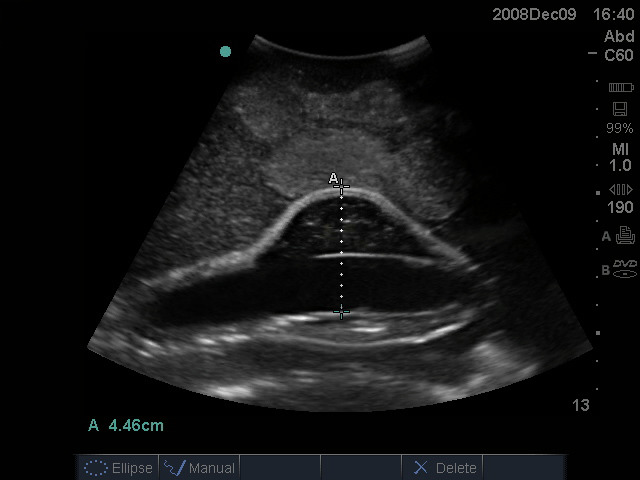

腹主动脉瘤超声训练模型

型号:PC-BP004

模型数据源于真实成人躯干模型,具有腹主动脉瘤和相应血管的内在解剖结构,可用于培训临床医生对腹部主动脉瘤进行超声探查、获取标准切面、测量大小等操作